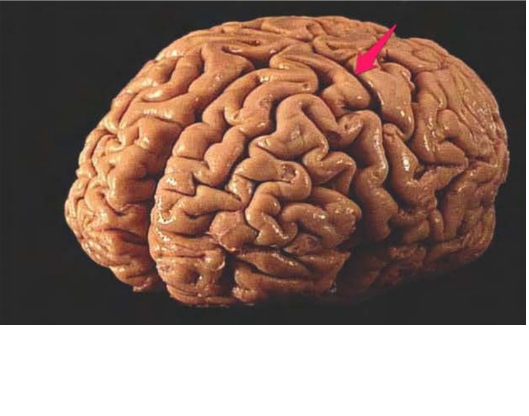

lobus parietalis Dex.

lobus temporalis sin.

sulcus lateralis sin.

sulcus centralis sin.

lobus frontalis dex.

lobus occipitalis sin.

fissura longitudinalis cerebri